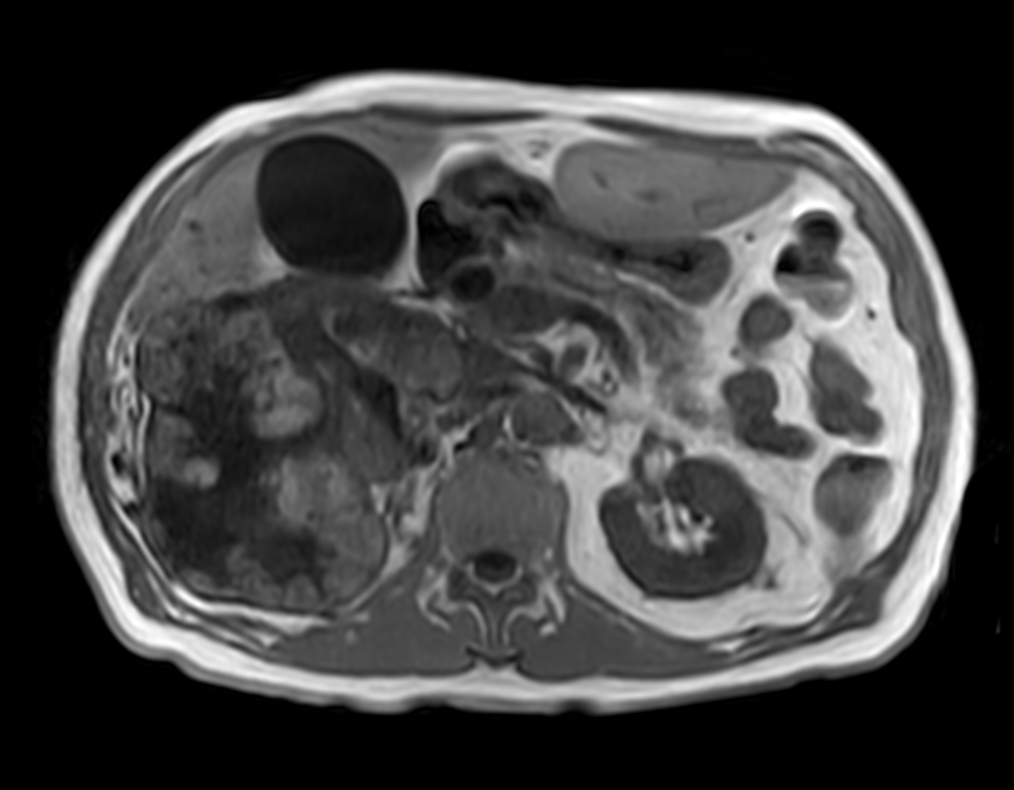

Patient with kidney tumor. ExamCard includes Compressed SENSE to shorten the breath hold time, VitalEye for touchless respiratory sensing, mDIXON XD FFE to acquire up to four image types in one single scan, DWIBS to achieve high contrast between background and lesions and bTRANCE for non-contrast time-resolved imaging.

bTFE - VitalEye Compressed SENSE